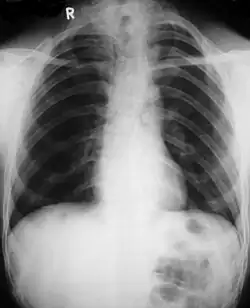

• Clavicles (collarbones) can be partly missing leaving only the medial part of the bone. In 10% of cases, they are completely missing.[10] If the collarbones are completely missing or reduced to small vestiges, this allows hypermobility of the shoulders including ability to touch the shoulders together in front of the chest.[11] The defect is bilateral 80% of the time.[12] Partial collarbones may cause nerve damage symptoms and therefore have to be removed by surgery.

Different features of the dysostosis are significant. Radiological imaging helps confirm the diagnosis. During gestation (pregnancy), clavicular size can be calculated using available nomograms. Wormian bones can sometimes be observed in the skull.[20]